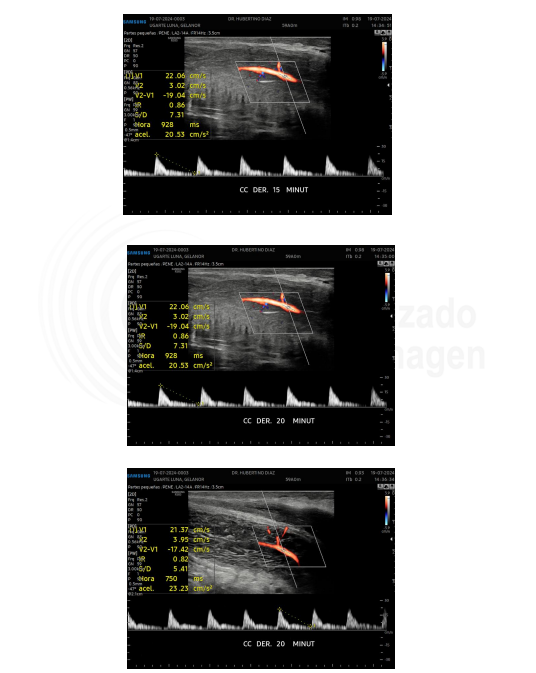

Ecografía doppler del mismo paciente con enfermedad de La Peyronie e inicios de disfunción eréctil

En el infome de la ecografía doppler se aprecian valores arteriales de pico sistólico máximo menores a 30 cm/s, lo que implica una insuficiencia arterial o de llenado. Así mismo los picos diastólicos permanenec menores a 5 cm%s, lo que indica que NO hay afectación venosa, cononcida como fuga venosa.